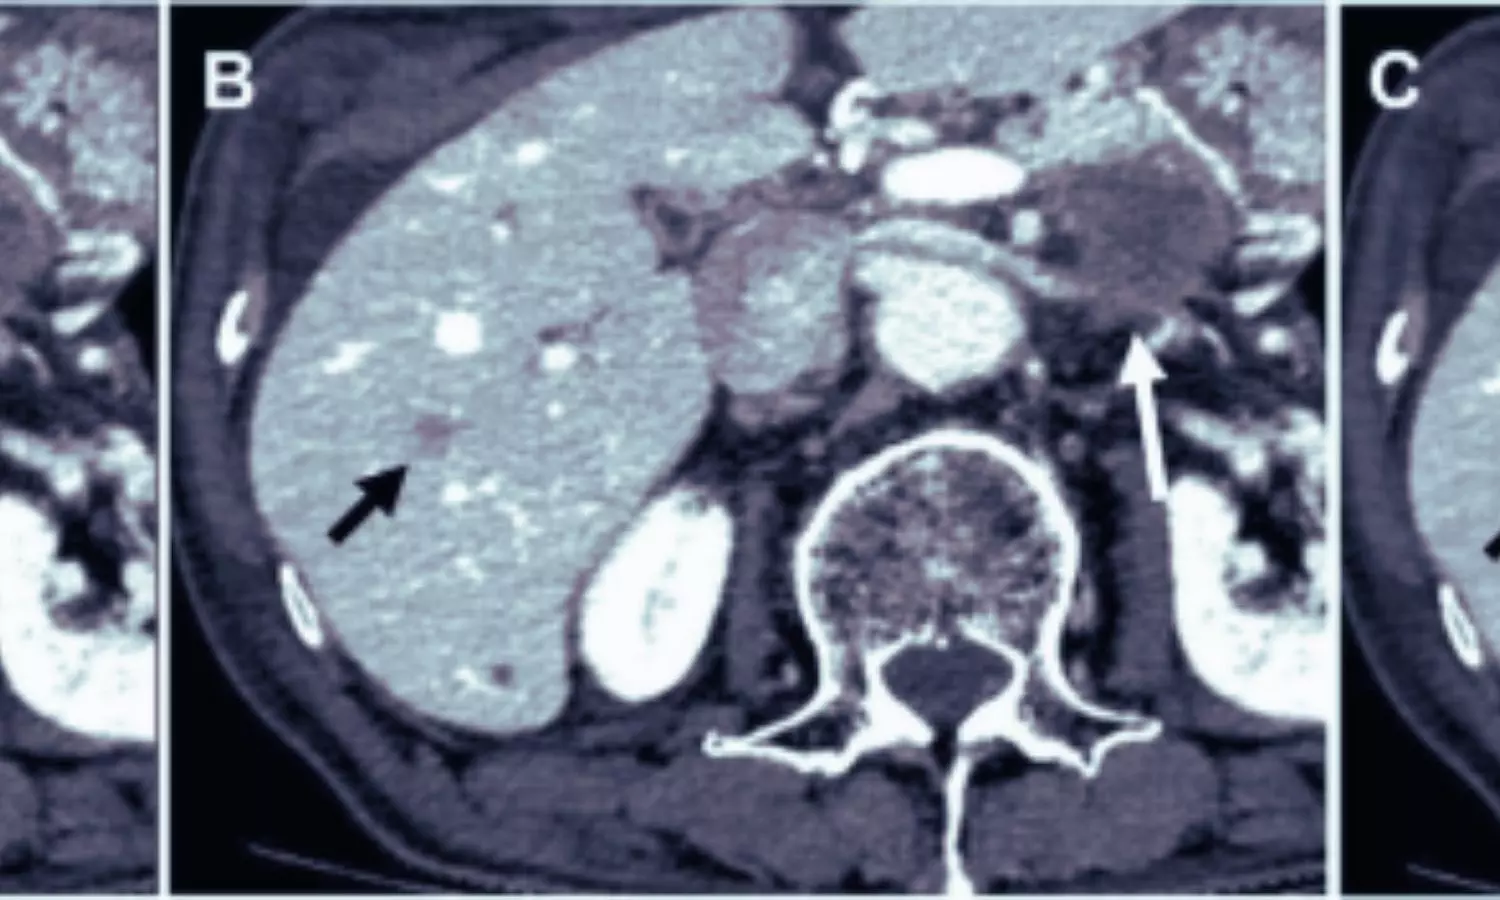

China: A new study published in Academic Radiology suggests that deep learning–based image reconstruction significantly enhances image quality in dual-energy CT portal venography, even when both radiation dose and contrast medium volume are reduced.The findings indicate that this advanced reconstruction approach could support safer and more reliable imaging for patients undergoing liver-related evaluations, including those being assessed for liver transplantation.Dual-energy CT portal venography (DE-CTPV) is essential for visualizing the portal venous system and guiding preoperative planning and postoperative follow-up in hepatobiliary surgery and liver transplantation. However, efforts to reduce radiation exposure and contrast-related risks often compromise image quality. Deep learning image reconstruction (DLIR) has emerged as a potential solution, though its effectiveness in dual-low dose DE-CTPV has remained uncertain.To address this, researchers led by Chong Meng from the Affiliated Hospital of Xuzhou Medical University, China, compared DLIR with adaptive statistical iterative reconstruction (ASIR-V) in a dual-low dose DE-CTPV setting. The study examined whether DLIR could preserve or enhance image quality across major portal venous structures despite reduced radiation and contrast use.Images were reconstructed using DLIR at medium and high strengths and ASIR-V at 50%. Image quality was assessed across the main, left, and right portal veins, splenic vein, and superior mesenteric vein using objective measures such as image noise, contrast-to-noise ratio, and signal-to-noise ratio, alongside radiologists’ evaluations of image clarity, edge sharpness, and diagnostic confidence.The study led to the following notable findings:Deep learning image reconstruction, particularly the high-strength setting, consistently outperformed ASIR-V across all evaluated vascular segments.DLIR-H significantly reduced image noise while achieving higher contrast-to-noise and signal-to-noise ratios.Improved noise reduction and signal quality enabled clearer visualization of portal venous anatomy despite lower radiation dose and reduced contrast volume.Radiologists gave DLIR-H the highest ratings for overall image quality, vascular edge sharpness, and diagnostic confidence.The dual-low dose protocol achieved a mean CT dose index volume of approximately 9.8 mGy and an effective dose below 5 mSv.The average contrast medium volume used was around 80 mL, reflecting substantial dose reduction.Image quality remained high under these reduced dose conditions when DLIR was applied.Use of 55 keV virtual monoenergetic imaging enhanced iodine contrast.DLIR effectively mitigated the increase in image noise associated with low-keV imaging, ensuring consistent and clear vascular delineation.According to the authors, these findings highlight the potential of DLIR to optimize DE-CT portal venography protocols. By maintaining high image quality while minimizing radiation and contrast exposure, DLIR may improve the safety profile of CT imaging for patients requiring repeated or detailed vascular assessments.The researchers conclude that “deep learning–based reconstruction offers a meaningful advantage over conventional iterative reconstruction techniques in dual-energy CT portal venography. Its ability to deliver high-quality images under dual-low dose conditions suggests it could become a valuable tool in routine clinical practice, particularly for liver transplantation planning and postoperative follow-up.” Reference:Meng C, Liu X, Wang Z, Long J, Wang C, Yang J, Sun B, Zhang D, Liu Z, Wang X, Sun A, Xu K, Meng Y. Deep Learning Image Reconstruction Improves Image Quality in Dual-Low Dose Dual-Energy CT Portal Venography Compared to Adaptive Iterative Image Reconstruction Algorithm-Veo. Acad Radiol. 2026 Jan 2:S1076-6332(25)01133-X. doi: 10.1016/j.acra.2025.11.047. Epub ahead of print. PMID: 41484021.